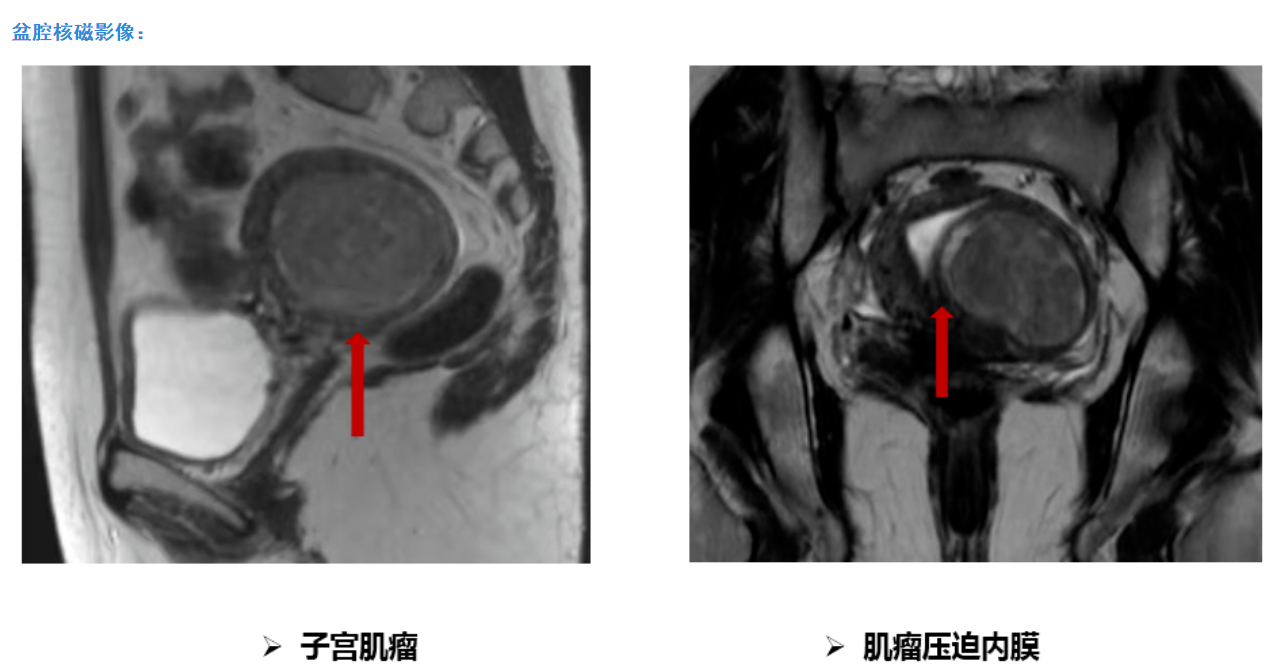

平素月经规律,5-6天/29天,量中,痛经(-),LMP:2021-10-24。3年前体检查妇科彩超提示子宫肌瘤,直径约2cm。无相关不适症状,建议定期复查。期间不定期复查彩超提示子宫肌瘤逐渐增大。10个月前无明显诱因出现经量增多,约为原来的2-3倍,伴血块,经期延长,最长达14天,月经周期未见明显改变,口服药物(具体不详)治疗未见好转。为明确诊治就诊我院门诊,查妇科彩超提示:子宫后壁可见6.99x5.35cm的低回声团,向前压迫子宫内膜,宫腔可见深度约0.55cm的无回声区,宫颈形态规则,内未见异常回声,子宫左侧可见1.75x1.21cm的低回声团,与子宫关系密切。建议住院手术治疗。

入院后在基础麻醉下行宫腔镜检查术。术中探查:探宫腔深8cm,宫腔形态基本规则,子宫后壁可见一直径约1.5cm肌瘤凸向宫腔,双侧输卵管开口可见。